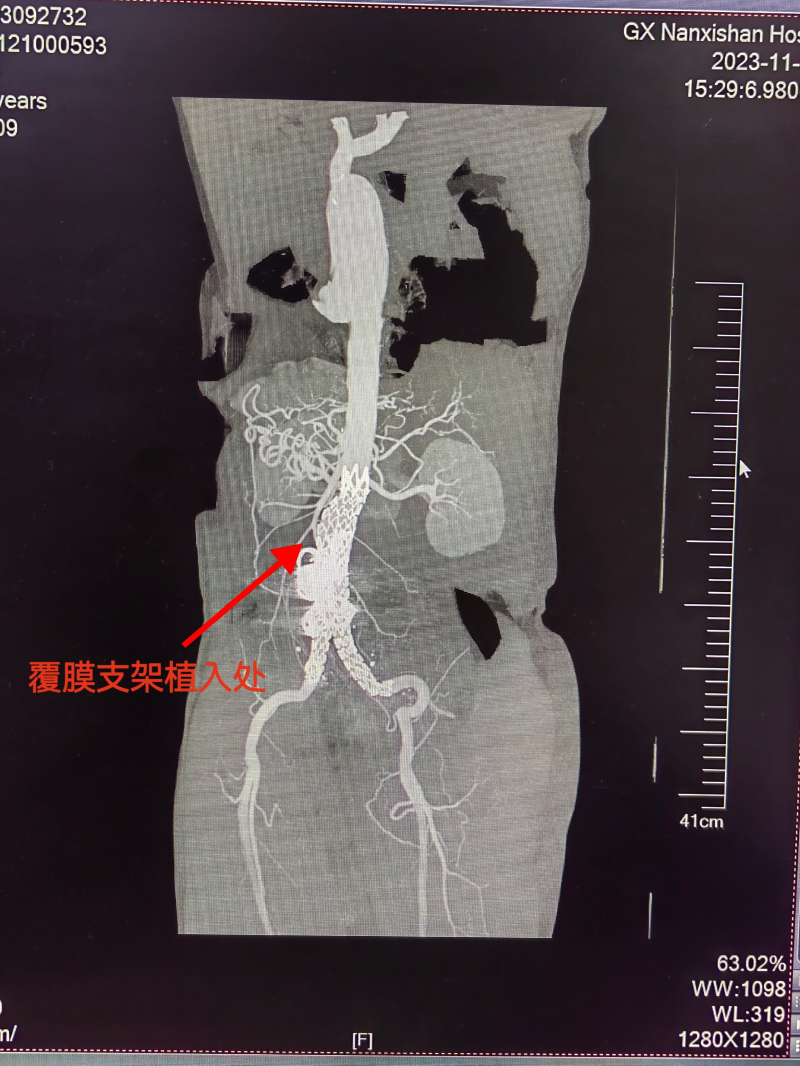

危急关头,该院血管外科第一时间组成由血管外科学术带头人、南溪山医院副院长胡长付、血管外科白韬主任为首的手术团队,讨论该患者的手术方案,为了保证患者生命安全,减少创伤,降低手术风险,根据腹主动脉瘤影像资料所提示,手术团队决定实施腹主动脉瘤腔内覆膜支架隔绝术。

在团队的通力协作下,顺利为患者实施了腹主动脉瘤腔内覆膜支架隔绝术,成功挽救了患者的生命,精准拆除了这颗致命“炸弹”!术后第十天,李先生恢复良好,顺利出院,临行前,他特意向血管外科全体医护表示由衷地感谢。

据介绍,腹主动脉瘤是临床中一种极其凶险的血管性疾病。容易破裂发生致命性大出血,短时间内直接威胁生命,患者腹主动脉瘤破裂,传统方法只有切开开放予大血管置换术,手术创伤大、出血较多,术后恢复慢。南溪山医院血管外科团队在患者腹主动脉瘤破裂的情况下,坚决实施微创下腹主动脉瘤腔内覆膜支架隔绝术,在创伤小、出血少的情况下成功挽救患者生命,体现了手术团队过人的胆略与医术。